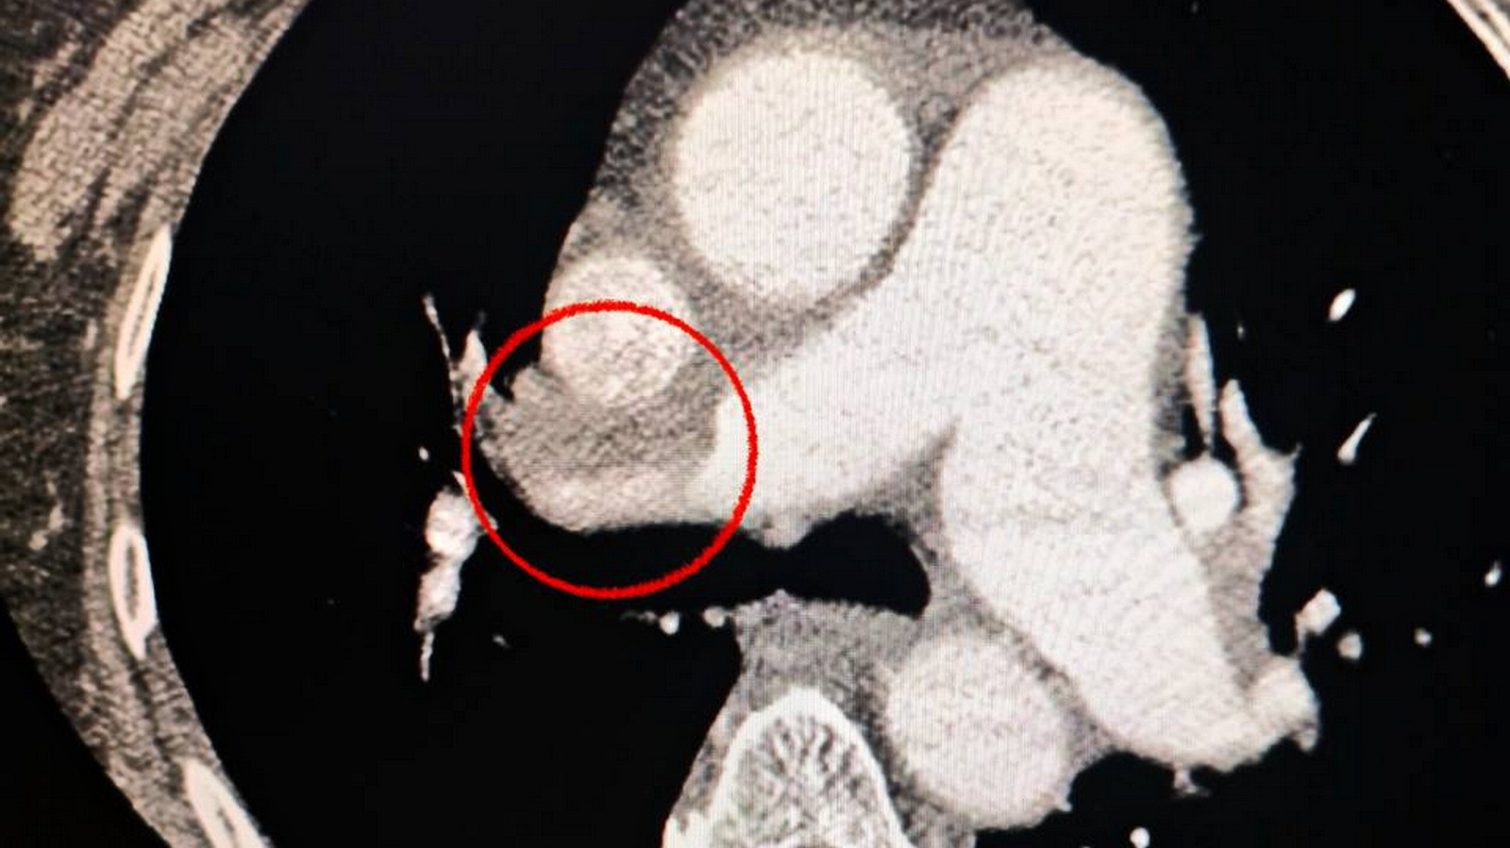

Також медики звернули увагу, що пацієнтці важко дихати, тож додатково обстежили легені. Діагноз ускладнився ще й тромбоемболією легеневої артерії.

Мультидисциплінарна команда лікарів ухвалила складне, але життєво необхідне рішення — провести одночасну тромбектомію з мозкової та легеневої артерій.